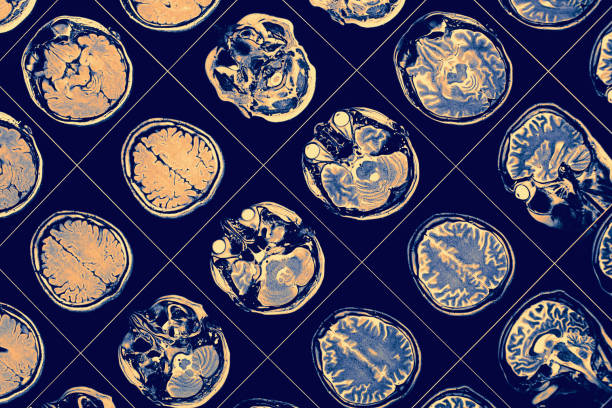

Μια πρόσφατη μελέτη που δημοσιεύτηκε στο Restorative Neurology and Neuroscience διαπίστωσε ότι η αύξηση της ροής του αίματος χρησιμοποιώντας μικρορεύματα μπορεί να είναι ένας αποτελεσματικός τρόπος για τη θεραπεία των συμπτωμάτων της γνωστικής εξασθένησης, της απώλειας όρασης και της κόπωσης σε άτομα με μακροχρόνια COVID. Οι συγγραφείς της μελέτης προτείνουν ότι οι αλλαγές στην υγεία των αιμοφόρων αγγείων, ειδικά στα μικροαγγεία, η μειωμένη ροή αίματος και η έλλειψη οξυγόνου είναι η κύρια αιτία των συμπτωμάτων του κεντρικού νευρικού συστήματος σε άτομα με COVID-19. Η έλλειψη οξυγόνου, μειώνει τη μεταβολική δραστηριότητα και αποσιωπά τους νευρώνες ή τα κύτταρα του νευρικού συστήματος.

Ερευνητές στο SAVIR-Center στο Μαγδεμβούργο της Γερμανίας, θεράπευσαν δύο γυναίκες με μακρά συμπτώματα COVID χρησιμοποιώντας μη επεμβατική εγκεφαλική διέγερση (NIBS) για να καταλάβουν εάν η νευροτροποποίηση θα μπορούσε να ενισχύσει τη ροή του αίματος και να αναστρέψει την οπτική βλάβη. Οι ερευνητές παρείχαν διέγερση εναλλασσόμενου ρεύματος των ματιών και του εγκεφάλου και ολοκλήρωσαν τις γνωστικές αξιολογήσεις πριν και μετά τη θεραπεία. Οι συμμετέχουσες έλαβαν 10-13 συνεδρίες θεραπείας διάρκειας 30-45 λεπτών η καθεμία. Οι ερευνητές παρείχαν για λίγο ηλεκτρικά ρεύματα μέσω ηλεκτροδίων που ήταν συνδεδεμένα στο μέτωπο ενώ οι συμμετέχουσες κάθονταν. Μετά τη θεραπεία, οι γυναίκες ξεκουράστηκαν για 15 λεπτά.

Η μελέτη διαπίστωσε ότι η μη επεμβατική νευροτροποποίηση με χρήση NIBS βελτίωσε την απώλεια οπτικού πεδίου σε λιγότερο από 4 ημέρες. Οι ερευνητές παρατήρησαν βελτιωμένη ρύθμιση των αιμοφόρων αγγείων στις περιφερικές αρτηρίες και φλέβες, με «όλες τις φλέβες» να παρουσιάζουν βελτιωμένη μέγιστη διαστολή των αγγείων κατά 113% και τις περιφερικές φλέβες να παρουσιάζουν κατά μέσο όρο 300% αλλαγή στη διαστολή των αγγείων μετά τη θεραπεία με NIBS. Εκτός από προβλήματα όρασης, οι συμμετέχουσες είχαν αναφέρει σοβαρά γνωστικά συμπτώματα. Και τα δύο βελτιώθηκαν μετά τη θεραπεία, με τη μία συμμετέχουσα να δείχνει επίσης θετική ανάκαμψη 40-60% στα γνωστικά τεστ.